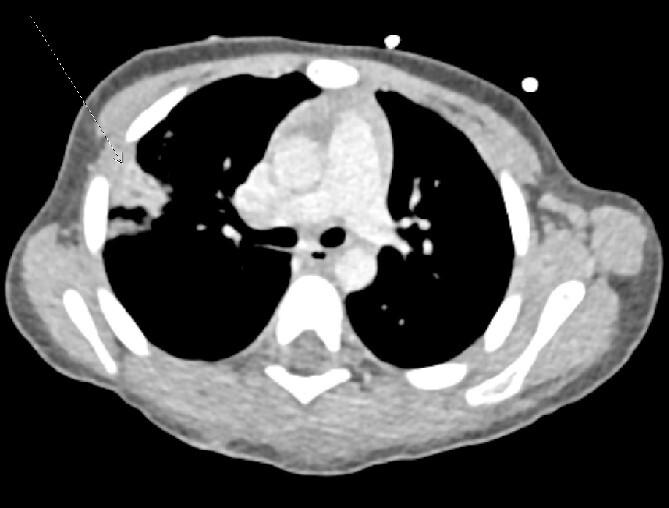

Cerebrospinal fluid (CSF) leakage is a known sequela of open traumatic skull fractures within the pediatric traumatic brain injury population. Black bears are a known entity within the region of northeast Pennsylvania. It is plausible to have a bear-human interaction resulting in significant bodily injury. A 15-month-old male presented in May 2023 as a level 1 trauma alert for a concerning wound at the base of the skull leaking clear fluid; suspicious for CSF. As a result of this interaction, significant bodily injury can occur, such as CSF leaks and traumatic skull fractures. Living in a region within a known bear population poses a minimal risk of injury. Pediatric populations are usually at a low risk for traumatic CSF leaks. Most of the CSF leaks will resolve spontaneously, without acute surgical intervention, as was seen in our patient after a traumatic bear mauling.

脑脊液(CSF)漏是小儿创伤性脑损伤人群中开放性创伤性颅骨骨折的已知后遗症。黑熊是宾夕法尼亚州东北部地区的已知物种。熊与人之间的互动导致严重身体伤害是有可能的。一名15个月大的男性于2023年5月因颅骨底部一处令人担忧的伤口有清亮液体漏出(怀疑为脑脊液)而作为1级创伤警报就诊。这种互动可能导致严重身体伤害,如脑脊液漏和创伤性颅骨骨折。生活在已知有熊的地区会带来最小的受伤风险。小儿人群通常发生创伤性脑脊液漏的风险较低。大多数脑脊液漏会自行缓解,无需急性手术干预,就像我们的患者在被熊严重袭击后那样。